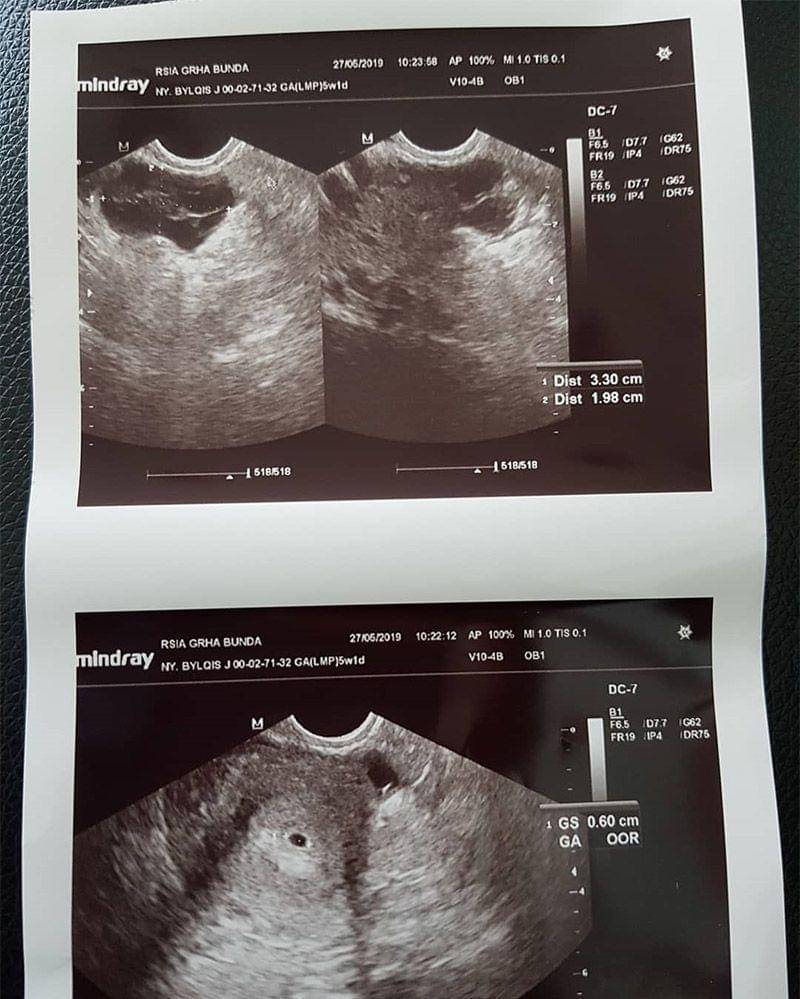

Ketika usia kandungannya masuk trimester awal yakni 8 minggu, Bylqis menuliskan sebuah cerita singkat mengenai penantian di Instagram pribadinya.

"Kita sama-sama berjuang ya de supaya kita bisa ketemu. Bertahun-tahun Umi nggak pernah lelah, tiap bulan nggak pernah kelewat buat test pack dan bertahun-tahun ekspresi kecewa tiap bulan test pack itu nggak tergambarkan. Sampai akhirnya Umi nyerah dan Ayah udah ngajak bayi tabung karena kakak Taza udah rewel bilang pingin punya adek. Bulan itu sudah telat seminggu, tetapi Umi nggak ada gairah buat test pack. Kakak Taza tiap hari nyuruh test pack. Ya demi kakak Taza, Umi tespek akhirnya ketika hasilnya positif, luar biasa rasanya sudah tidak bisa digambarkan dengan kata-kata. Lalu Umi menyadari the power of pasrah, kata dokter masih rawan, kuat-kuat dan sehat ya dede. Umi Ayah dan Kaka Taza udah nggak sabar pingin ketemu dede bayi," tulis Bylqis pada unggahannya bulan Juni lalu.